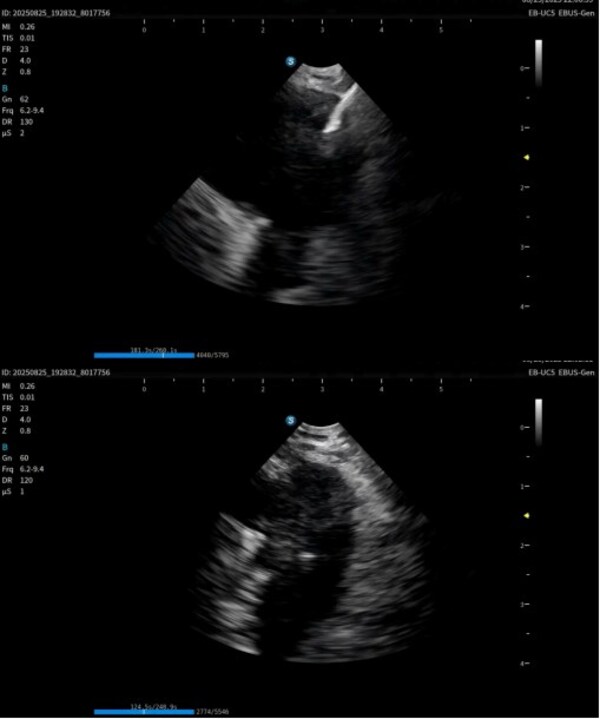

本次获证标志着开立医疗实现国内首家在该领域做到产品系列最齐,功能最完备的超声电子支气管内窥镜系统:超声电子支气管内窥镜+高清电子支气管镜+超声微探头+一体式超声内镜主机+分体式超声内镜主机,可满足不同呼吸诊疗术式临床应用需求。

作为在呼吸诊疗领域的重磅产品,本次在产品创新设计上和工艺技术上取得了重大突破,显著提升了光学图像和超声图像的质量,同时镜体保持了良好的操作性,在钳镜比和视野角综合参数可达到全球同类产品最佳性能。目前在临床应用表现突出,取得了专家的认可和好评。

超声电子支气管内窥镜凭借其"微创、精准、安全"的特点,已成为呼吸介入领域的核心技术之一。开立医疗全系列产品全面上市可为肺部肿瘤、纵隔病变提供管内清晰光学影像,管外高清声学断层组织及血流影像,提供精准可视化介入操作,为疾病的诊断提供更精准、更安全、更高效的一体化诊疗解决方案。